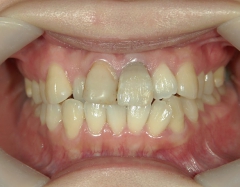

矯正歯科 治療前矯正歯科 治療前

no.37_7548_治療前_右.JPGno.37_7548_治療前_正面.JPGno.37_7548_治療前_左.JPG